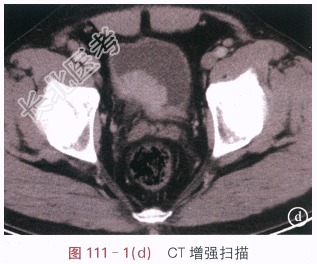

读片分析:图111-1(a)IVP示右侧肾脏功能受损,右侧肾盂、肾盏及输尿管未能显影;图111-1(b)IVP示膀胱内右侧壁类圆形充盈缺损,直径约4.5cm,边缘光滑;图111-1(c)CT平扫示膀胱右后壁见软组织肿块,大小约4.5cm×2.5cm,边缘较光整,周围膀胱壁增厚、僵硬,周围脂肪间隙清晰,右侧输尿管下端扩张;图111-1(d)CT增强示膀胱壁肿块明显强化,强化均匀。结合病史,患者诊断为膀胱癌。